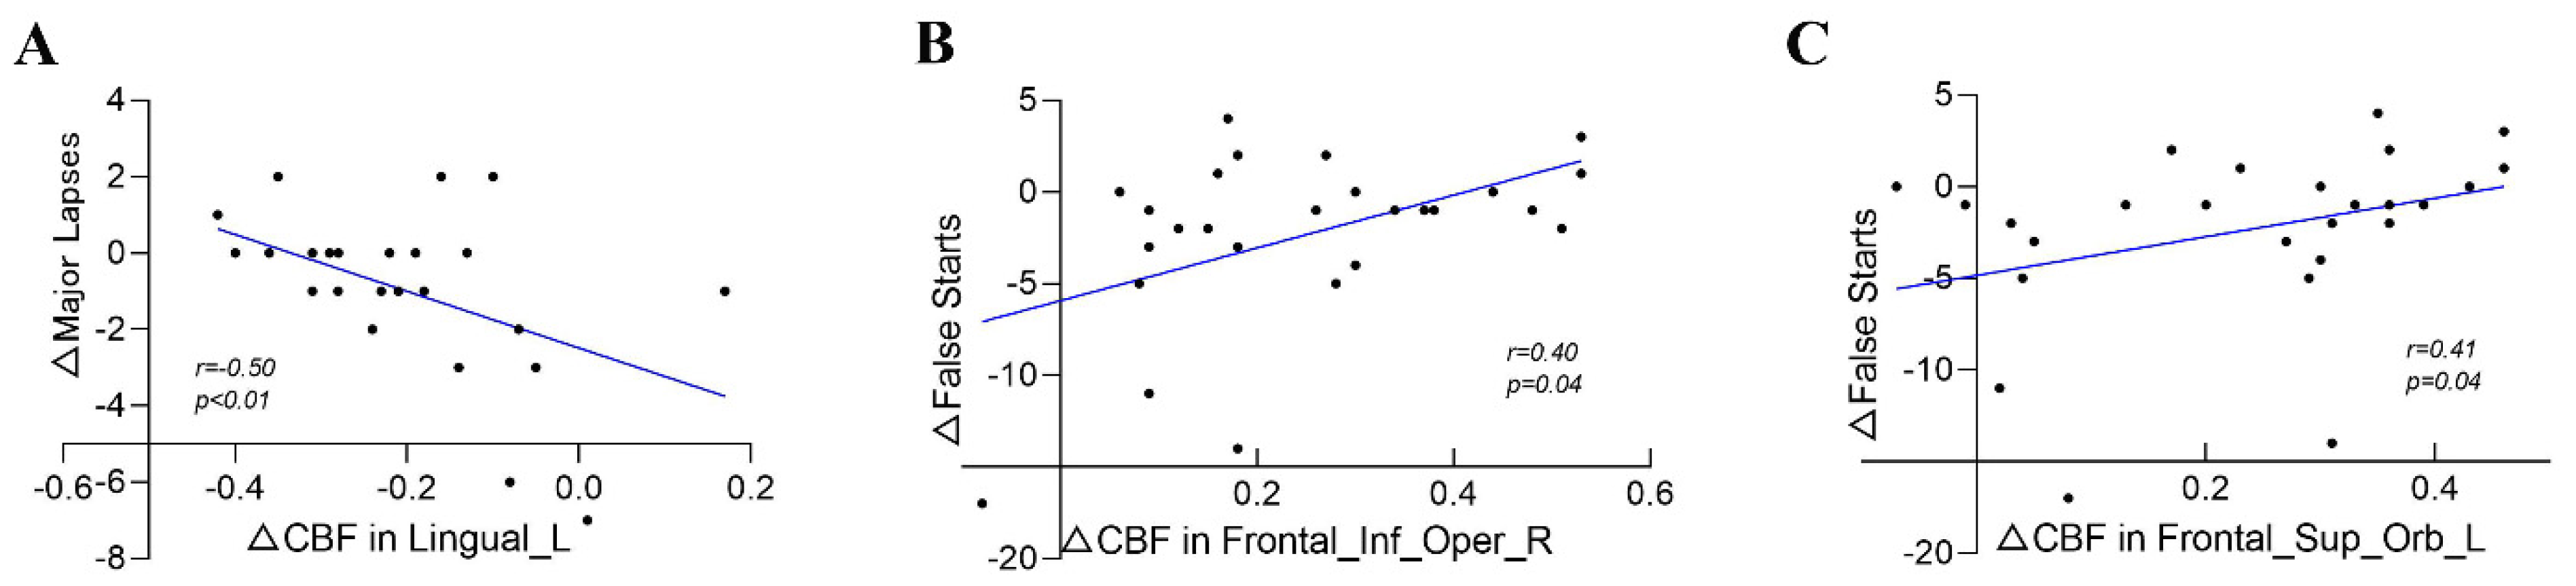

3.4. Correlation between PVT Changes and CBF Changes

| Frontal_Mid_Orb_L | 0.25 | 0.22 | 0.26 | 0.19 | 0.30 | 0.14 | 0.29 | 0.15 | 0.10 | 0.63 |

| Frontal_Inf_Oper_R | 0.40 | 0.04 | 0.23 | 0.25 | 0.35 | 0.08 | 0.31 | 0.12 | 0.03 | 0.89 |

| Frontal_Sup_Orb_L | 0.41 | 0.04 | 0.32 | 0.11 | 0.21 | 0.31 | 0.34 | 0.09 | 0.16 | 0.45 |

| Lingual_L | −0.38 | 0.05 | −0.26 | 0.20 | −0.50 | 0.01 | −0.39 | 0.05 | −0.09 | 0.67 |